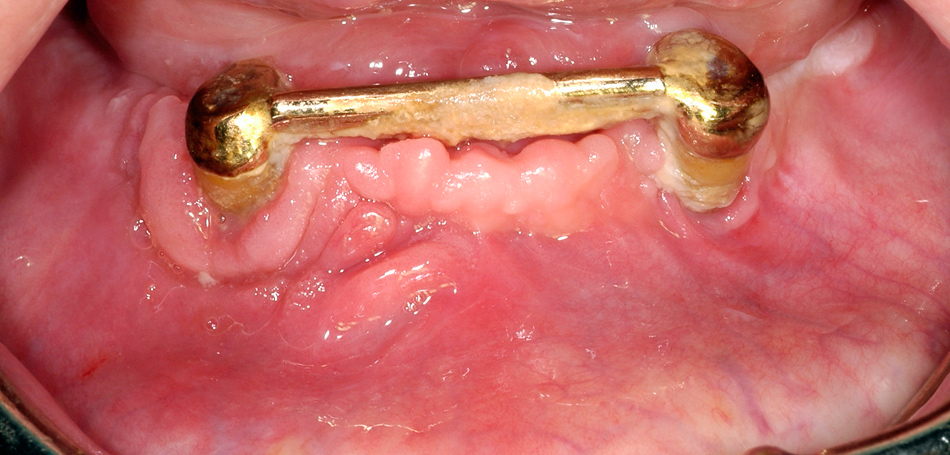

Figure 4

Same patient as figure 2 shows the situation after surgical treatment of BRONJ with complete remission without any remaining dehiscence of the soft tissue.

Of the surgically treated patients with osteoporosis, 95% showed complete remission (fig. 4), and one female patient showed partial remission with a small area of remaining exposed bone, but had no complaint. Complete remission was achieved in 71% of surgically treated patients with underlying malignant disease; partial remission was achieved in seven patients, and six patients showed no improvement at the surgically treated site.